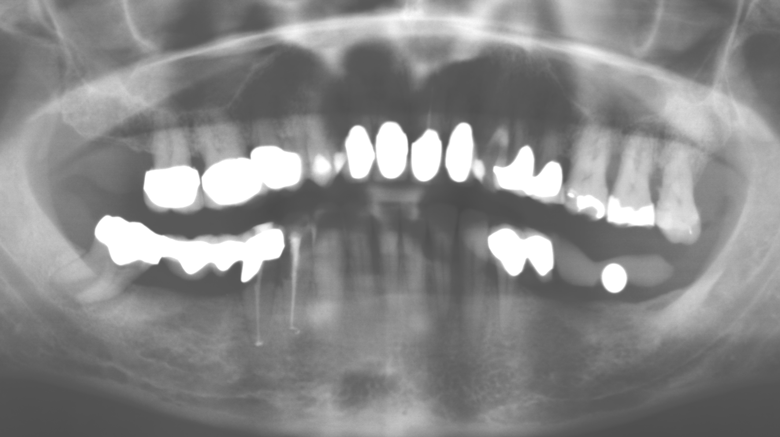

Fig. 1: Panoramic radiograph of initial situation in 2004.

Description of patient case

A 52-year-old patient presented in our clinic for the first time in 2004 following tooth loss in the third quadrant, expressing a desire for a new prosthetic restoration. Periodontal and radiological diagnostics revealed the need for extensive periodontological treatment. In addition, teeth 48, 28 and 27 were attributed a very poor prognosis and were subsequently extracted (Fig. 1). Following the successfully completed, systematic periodontological treatment, a fixed dental implant was inserted with the introduction of five implants in tooth regions 35, 36, 37, 46 and 47. Prosthetic treatment of the natural teeth was effected with veneered zirconium dioxide ceramic crowns; the implants were composed of two-piece, individual zirconium dioxide abutments and similarly veneered crowns made of a zirconium dioxide ceramic (Cercon base colored, Dentsply Sirona Lab). Definitive insertion of the prosthetic restoration occurred in 2005.

The ten-year check-up revealed no indications of advancing clinical attachment loss or peri-implant bone substance loss (Fig. 3).